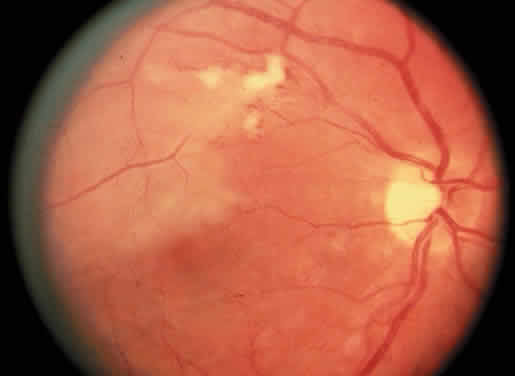

Protein S is a nonenzymatic cofactor necessary for the anticoagulant activity of activated protein C. Protein S by itself also has anticoagulant activity by forming a complex with C4b binding protein, a regulatory protein of the complement system. Protein S deficiency is inherited as an autosomal-dominant trait. Unlike protein C deficiency or antithrombin III deficiency, heterozygous protein S deficiency is not as strong a risk factor for thrombosis. Retinal artery occlusion has been described with protein S deficiency.25,29 Figure 2 shows a pregnant woman with protein S deficiency and a branch retinal artery occlusion (see Fig. 2).

|